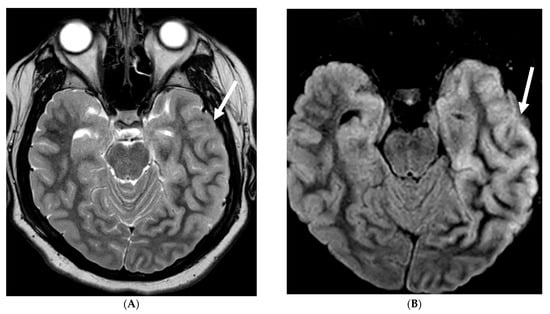

5.1. Viral Meningitis

Several viruses, such as enterovirus, herpes simplex virus (HSV)-1&2, mumps, varicella, and arbovirus, can infect children, out of which enterovirus is the most common. These organisms have variable LME, ranging from none to diffuse sulcal LME, best demonstrated on post contrast FLAIR over T1 images [97]. HSV is associated with poor prognosis due to associated parenchymal involvement. HSV-1 commonly causes oral herpes in contrast to HSV-2 which typically causes genital herpes in adults. An active/remote HSV 2 infection in the mother increases the risk of neonatal transmission if delivered vaginally.

HSV 2 typically causes diffuse cortical involvement with diffusion restriction, loss of gray white matter differentiation and basal ganglia involvement in early stages [98]. HSV 1 typically occurs in older children and adolescents and leads to asymmetric temporal lobe involvement with relative sparing of the basal ganglia (Figure 19).

Figure 19.

17-day-old girl with seizures. Axial T2 (A), axial DWI (B), axial T1 post contrast (C), short TE spectroscopy (D) and coronal T2 (E): There is loss of gray white matter differentiation indicating edema in bilateral frontal lobes (arrows). Extensive ischemic changes involving bilateral frontal, bilateral parietal lobes, bilateral perisylvian regions, bilateral thalami (curved arrows). Extensive LME is identified in the effected regions (dashed arrows). Abnormal elevation of lipid/lactate in both basal ganglia and white matter (open arrows). The above constellation of features are concerning for meningitis/cerebritis. Follow up MRI 5 weeks later demonstrates evolution of extensive ischemic changes into extensive cystic encephalomalacia and gliosis in the supratentorial brain, with ex vacuo enlargement of the ventricular system. CSF analysis: HSV-2.